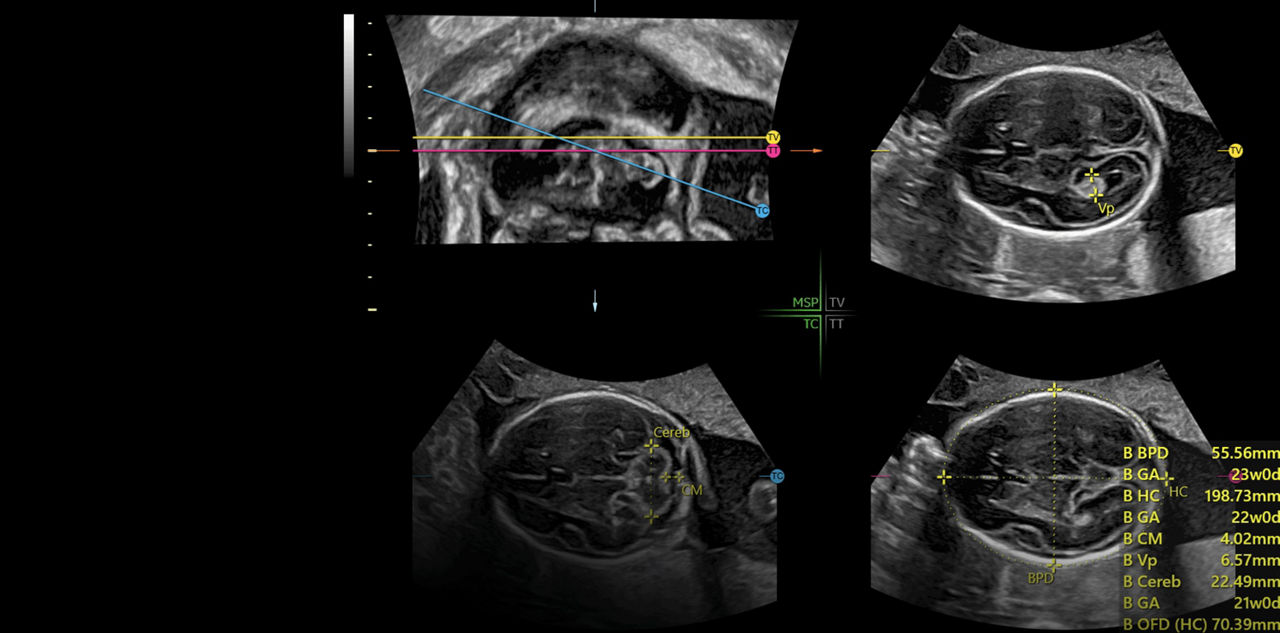

Extraordinary clarity and definition so you can focus on early detection and intervention.

Generate spectacular 2D/3D and color Doppler images with increased penetration and stunning clarity, to help visualize critical details needed for diagnostic assurance. The Lyric Architecture unlocks new imaging and processing power to expand your imaging capabilities for years to come